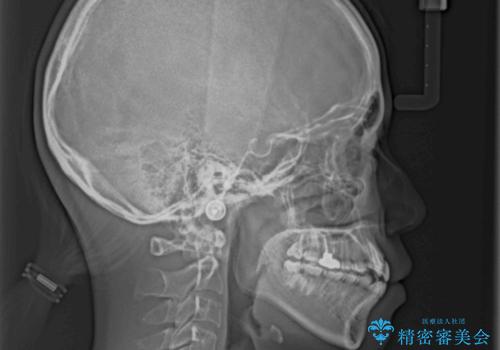

- 上の八重歯を気にして来院された患者様です。

受け口傾向にあるため、上顎前歯の叢生解消とともに下顎前歯を後方へ移動させることを目的とし、上下左右の第一小臼歯4歯を抜歯することとしました。

受け口傾向の方の下顎抜歯矯正では、下顎前歯の歯肉が退縮することがあります。前歯を移動させるときには、歯肉退縮が起こらないように工夫する必要があります。